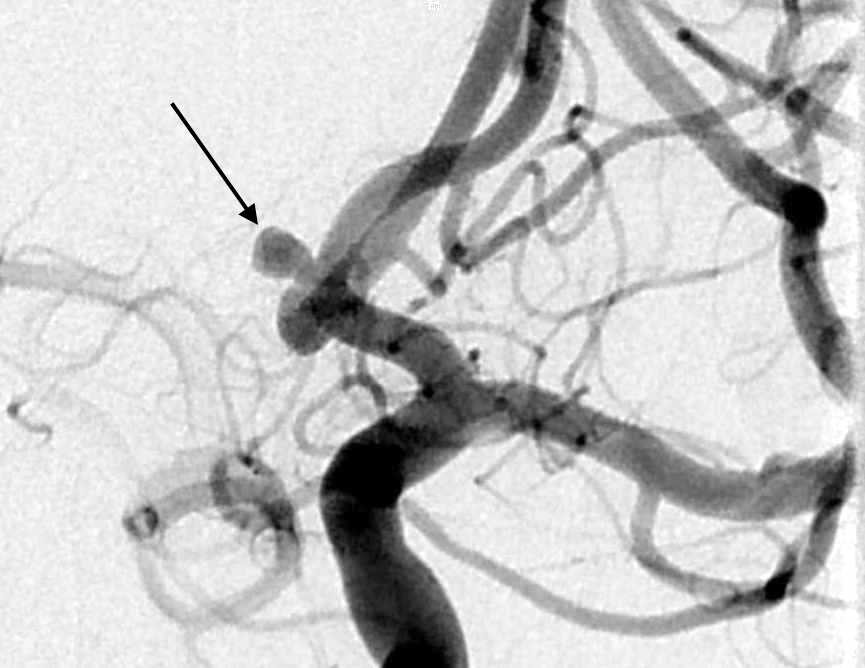

脳動脈瘤は脳にできた「血管のこぶ」であり、破裂すると「くも膜下出血」という生命を脅かす重大な病気にあることがあります。脳ドックなどで発見されて破れる前に手術をすることもあり、破裂しても再破裂を予防する目的で手術を行います。血管内治療では動脈瘤の中にコイルと呼ばれる柔らかい金属を詰めて固めることにより出血を予防することが可能で、開頭術と比べ遜色のない有効性と安全性が確立されています。その際にはステントや風船(バルーン)を使って正常の血管を塞栓しないように工夫をすることで安全性を高めています。

脳動静脈奇形や硬膜動静脈瘻といった脳血管の病気に対する治療や、脳腫瘍支援手術として塞栓術により術中の出血量を減らすなど、様々な疾患に対し脳神経外科と連携して脳血管内治療をおこなっています。